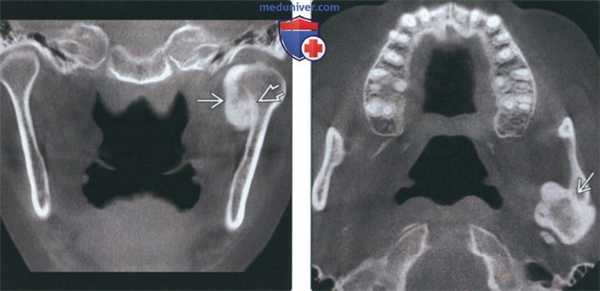

(Слева) На корональной КЛКТ на наружной поверхности шейхи левого мыщелка определяется компактная остеома, образованная плотной костью. Опухоль имеет широкое основание, ровные округлые симметричные контуры.

(Справа) На аксиальной КЛКТ у этого же пациента определяется остеома исходящая из кортикальной пластинки, в остальном имеющей нормальную толщину и плотность. Опухоль симметрична, форма мыщелка в остальном не нарушена.

(Слева) На корональной КЛКТ определяется большая остеома в области шейки и головки левого мыщелка, представленная преимущественно плотной кортикальной костью. Кортикальная пластинка шейки мыщелка остается различимой, что помогает отличить остеому от остеохондромы.

(Справа) На аксиальной КЛКТ у этого же пациента визуализируется крупная остеома шейки нижней челюсти с фестончатыми краями, находящаяся скорее на широком основании, чем на ножке.